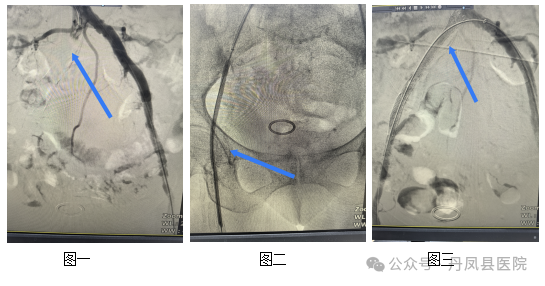

手术当日,交大一附院外周介入专家秦皓和神经内科副主任袁文超主治医师共同操作,采用穿刺左股动脉并翻山进入右髂总动脉,造影显示右侧髂总完全闭塞、远端未显影,侧枝代偿至髂外动脉远端显影,右股浅动脉近端重度狭窄,与CTA结果一致。导管配合导丝通过上述闭塞段成功,球囊扩张右髂、右股浅动脉,于右髂总-髂外置入支架,造影见右髂动脉闭塞开通,未见造影剂外溢,右股浅近端狭窄明显改善。术后患者诉患肢冷痛缓解,一周后满意出院。![]()

图一为右侧髂总动脉-髂外动脉闭塞;图二为球囊扩张血管成形;图三为支架植入闭塞血管开通效果。